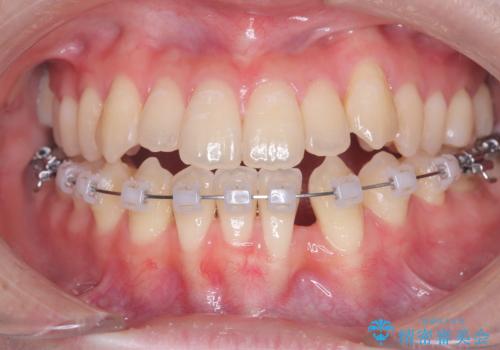

診査の結果、すでに下顎前歯の抜歯が行われていましたが、マウスピースの適合が著しく悪くなっており、歯が計画通りに動いていない状態でした。また、歯を支える骨の厚みや歯肉の薄さを考慮すると、このままマウスピースによる傾斜移動を続けるのは歯肉退縮(歯茎が下がること)のリスクが非常に高いと判断。

安全かつ確実に抜歯スペースを閉じ、咬み合わせを完成させるため、マウスピースから**ワイヤー矯正(マルチブラケット装置)**へ切り替えるリカバリープランを提案しました。

装置の変更と歯肉への配慮: ワイヤー矯正は歯の根(歯根)を平行に移動させる「歯体移動」を得意としています。本症例では、歯肉退縮を防ぐために、歯の傾きを精密にコントロールしながら抜歯スペースを閉じる必要がありました。ワイヤー装置を用いることで、インビザラインでは難しくなっていた三次元的な細かい調整を可能にしました。